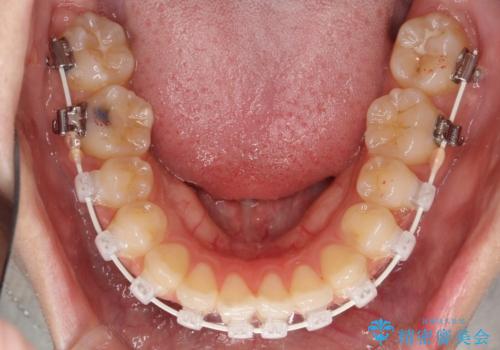

- 矯正装置

- 審美装置

- 前歯の凸凹を主訴に来院されました。

小臼歯抜歯(上顎4番)して矯正治療を行なったことで、口元もスッキリしました。